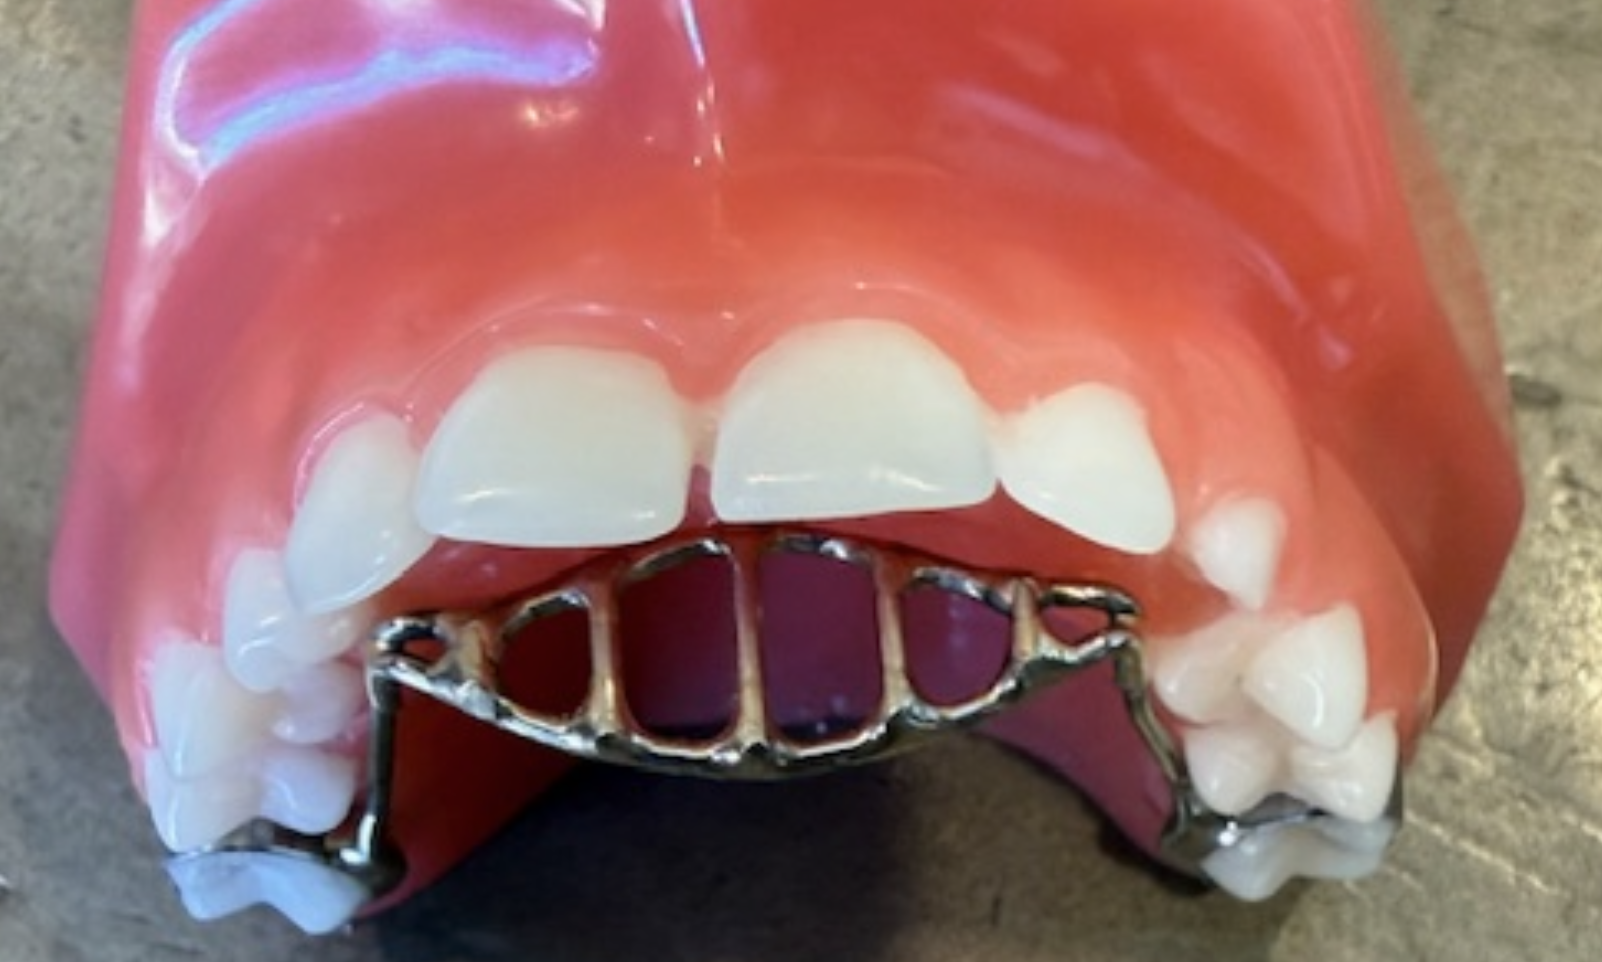

Posterior Crossbite

Top teeth are inside of bottom teeth.